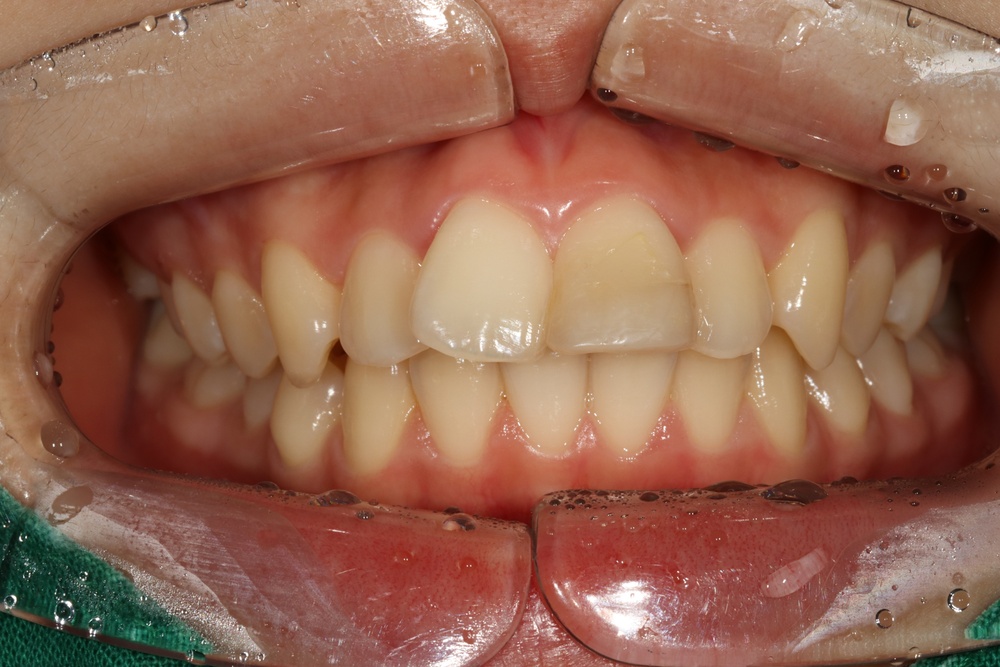

40대의 환자분으로, 앞니가 비뚤어서 코로나가 끝났을 때 마스크를 벗고 웃고 싶다고 하셨습니다.

충치가 많아서 교정 전 충치치료를 전반적으로 시행하고, 잇몸치료도 진행하였습니다.

중년기 교정에서 발생가능한 문제점(치아 사이 틈 발생가능성, 잇몸질환)충분히 설명드리고 시작하였습니다.

치아 배열이 거의 완성된 상태로 치료 전 말씀드렸던 치아사이의 틈(블랙트라이앵글)이 있습니다.

환자분과 상의 후 위쪽은 벌어진 공간을 레진으로 메꾸기로 하였습니다.

치아가 가지런해졌고, 윗니 치아 사이의 틈도 메꿔졌으며, 치아에 있던 충치도 모두 치료하였습니다.